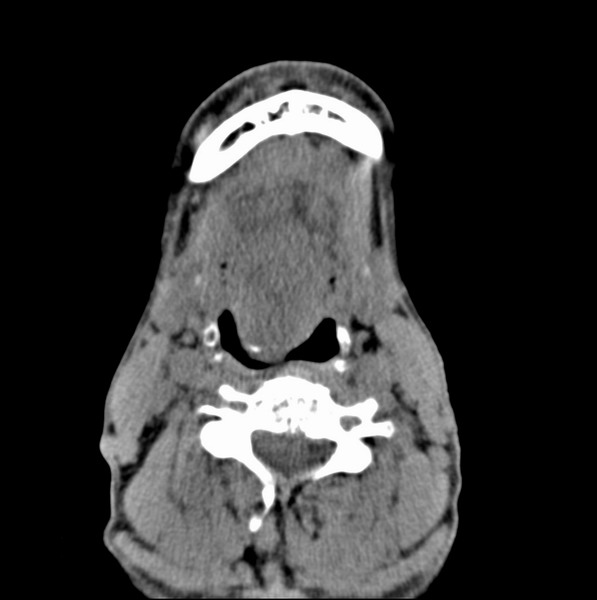

标题: CT19620:舌根肿物

男、60、舌根肿物。

舌垂直肌和横肌影处肿块影,边缘不规则,咽腭扁桃体及舌下间隙脂肪影消失,病变侵及口咽。

考虑-----舌根癌

舌跟软组织肿块,较大有坏死,钙化。结合年龄一般是恶性肿瘤。

舌根部较大软组织肿块,其内见坏死低密度区及钙化影;考虑舌根癌可能。